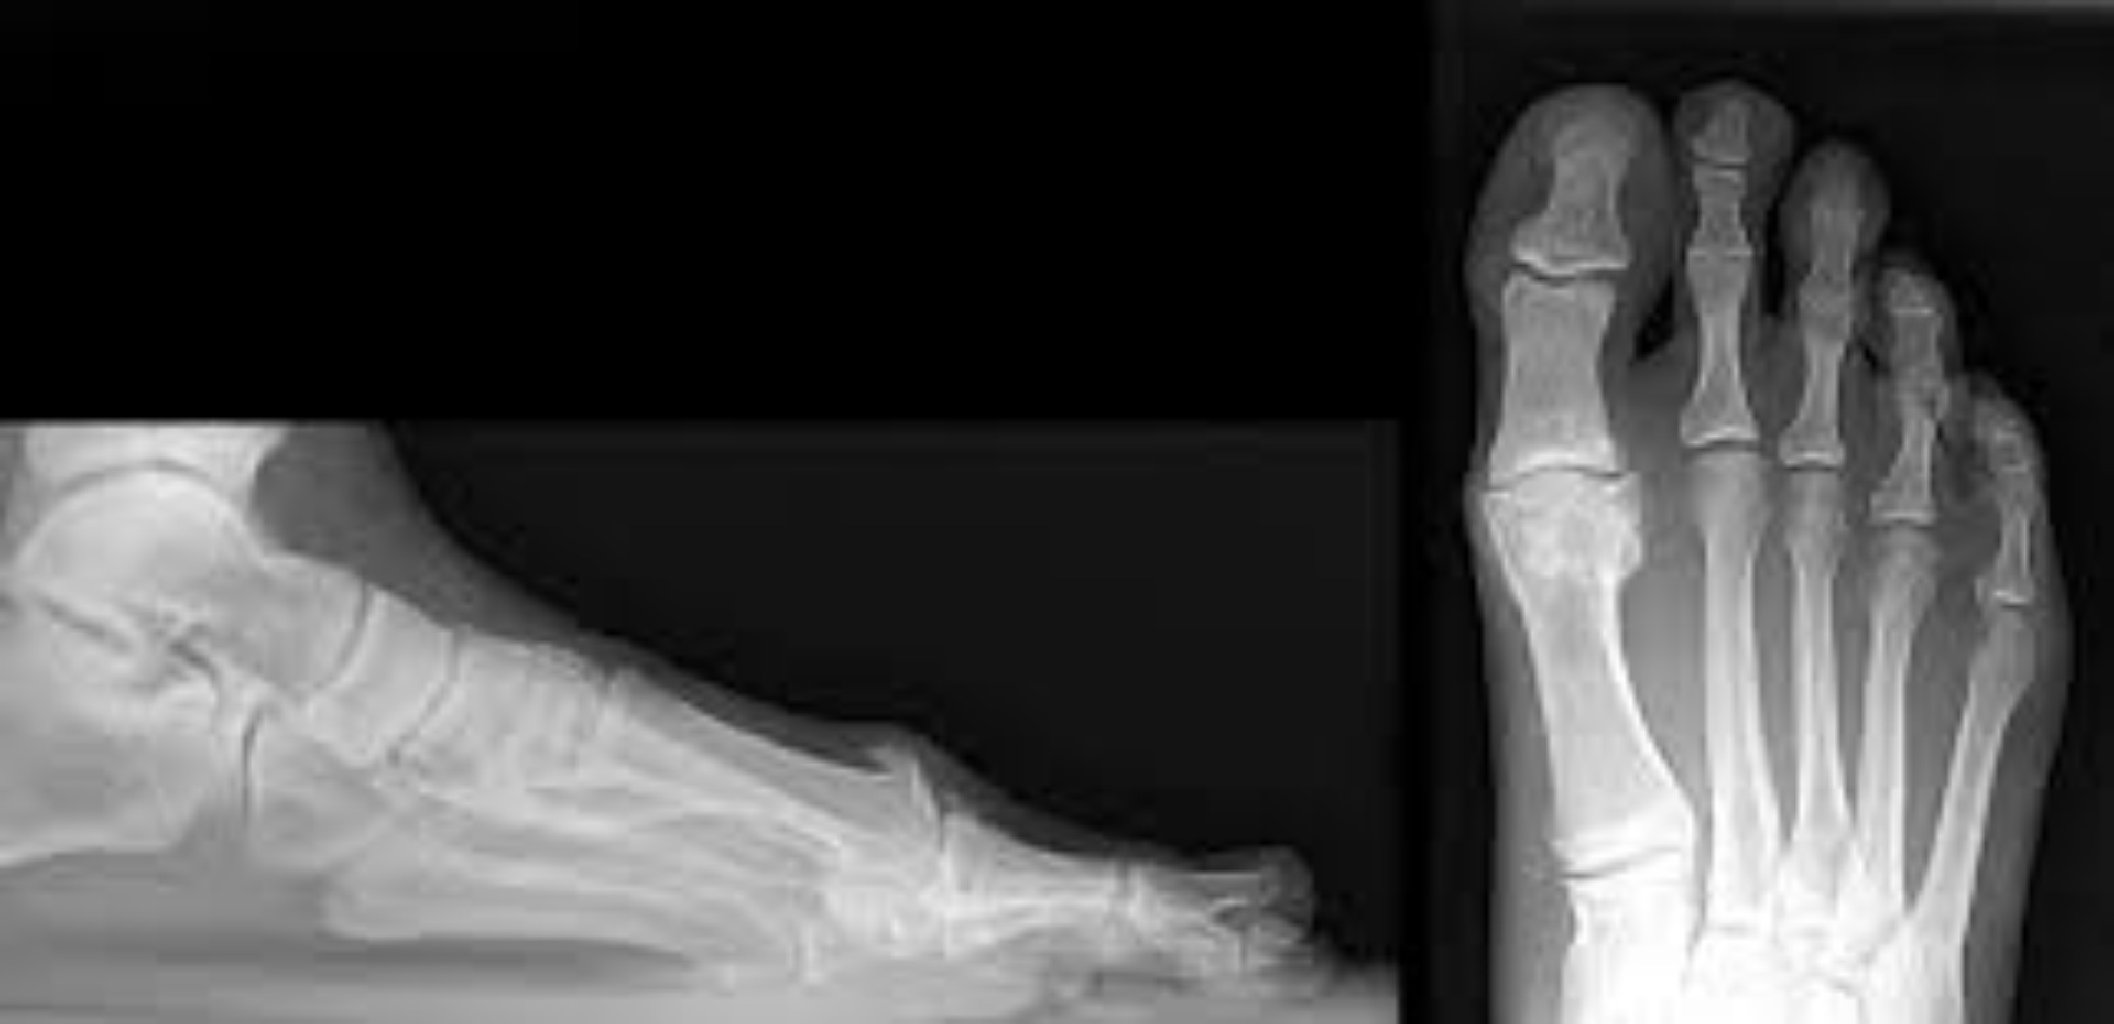

Hallux rigidus simptomlarına baş barmaq oynağında ağrı, şişlik, sərtlik və hərəkətin məhdudlaşdırılm ...

Hallux valgus genetik meyl, ayaq quruluşunda anormallıqlar, ayaqqabı seçimi və ayağa həddindən artıq ...

Kiçik barmaqların deformasiyası müəyyən sağlamlıq problemləri nəticəsində yarana bilər. Ən çox görül ...